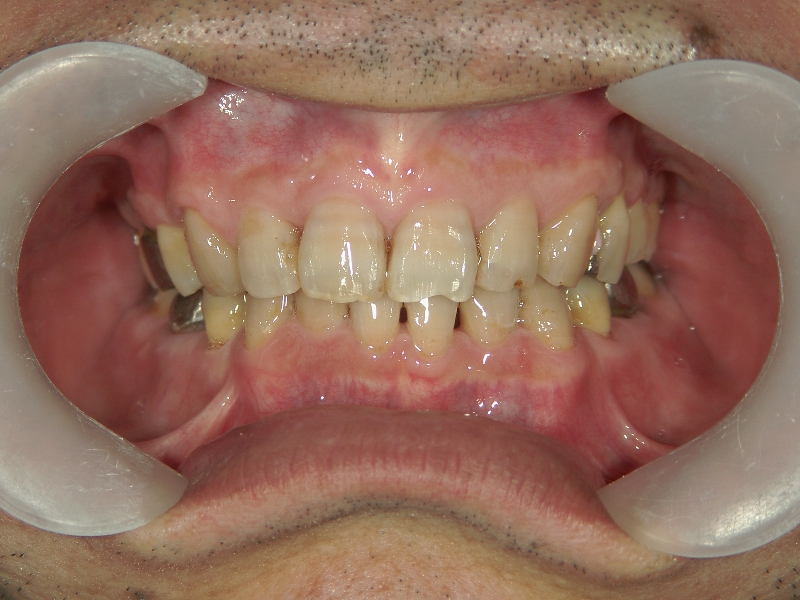

矯正歯科 治療前矯正歯科 治療前

主訴:下の歯がガタガタ。

矯正歯科 治療前 右上4番、左右下4番 計3本抜歯し、叢生を改善